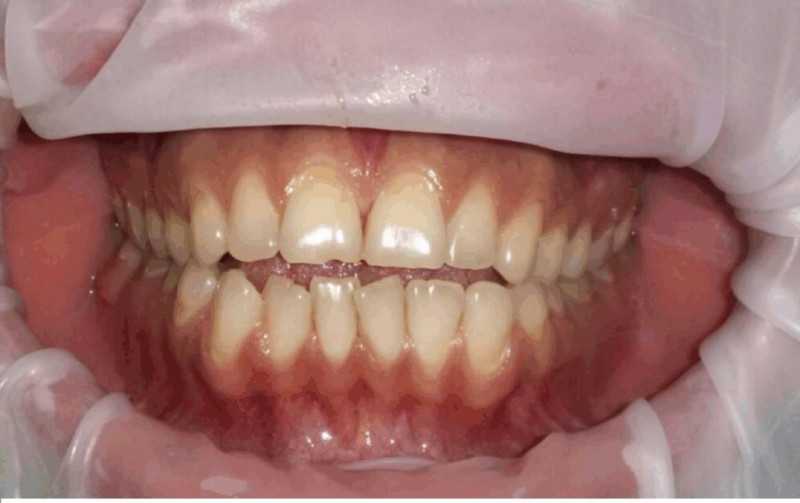

Отбеливание Zoom 4

В данном клиническом случае представлен выраженный дисколорит зубов за счёт пигментации и проведённого около 5 лет назад эндодонтического лечения зуба 1.1.

Доктор: Гатиятуллин Тимур Фанисович